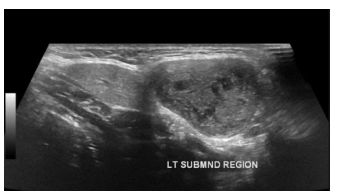

Você realiza o exame ultrassonográfico de glândulas

salivares de uma paciente do sexo feminino de 30 anos e

encontra a seguinte imagem. Assinale a alternativa

correta.